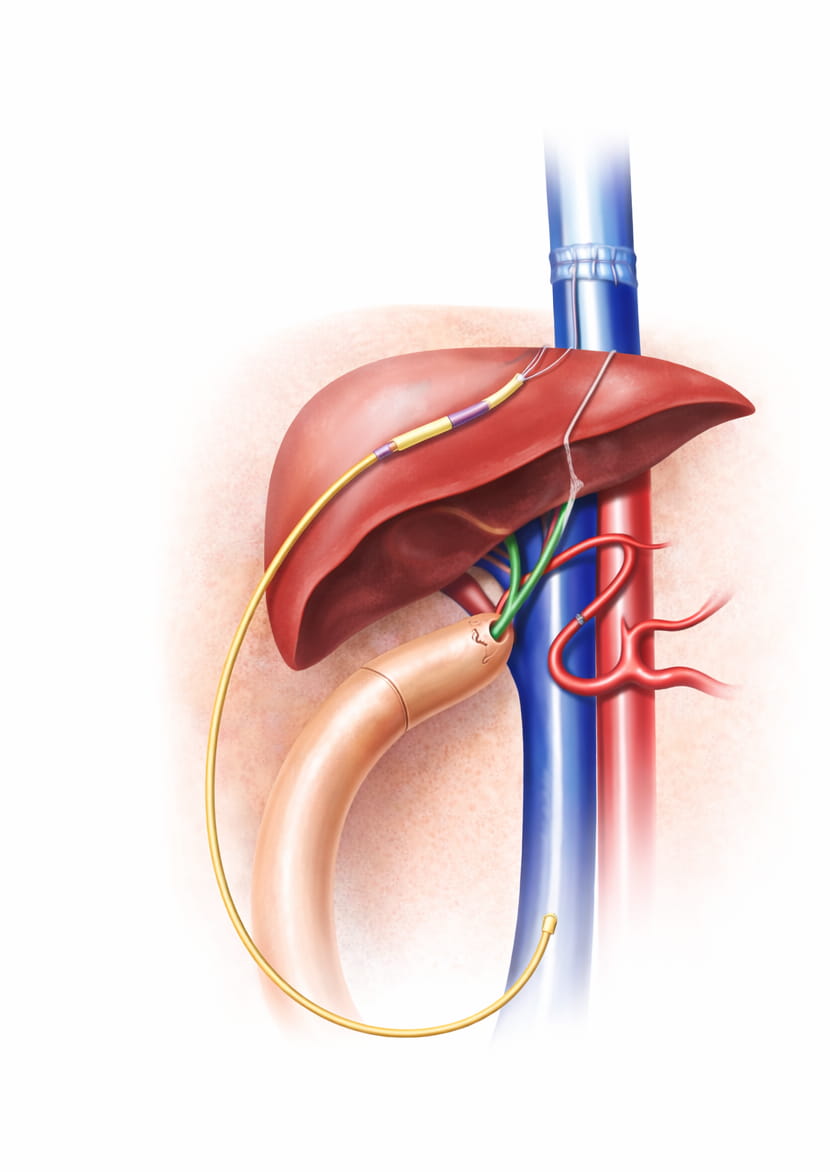

🎯 How It Works: Access Through the Liver

The procedure is performed using precision imaging in our specialized centers in Hyderabad and Chennai:

- Imaging Preparation: Ultrasound and Fluoroscopy (X-ray) are used simultaneously to visualize the liver and the veins within it.

- Percutaneous Entry: Under local anesthesia and sedation, a small needle is guided through the skin on the right side of the abdomen, passing through a small portion of the liver tissue.

- Venous Access: The needle enters one of the hepatic veins. A guide wire is then threaded into the Inferior Vena Cava and up toward the heart.

- Catheter Placement: A durable, “tunneled” catheter is placed over the wire. The “tunnel” under the skin helps anchor the catheter and provides a barrier against infection.

- Immediate Use: Once the position is confirmed, the catheter can be used immediately for life-sustaining treatments like hemodialysis or specialized infusions.